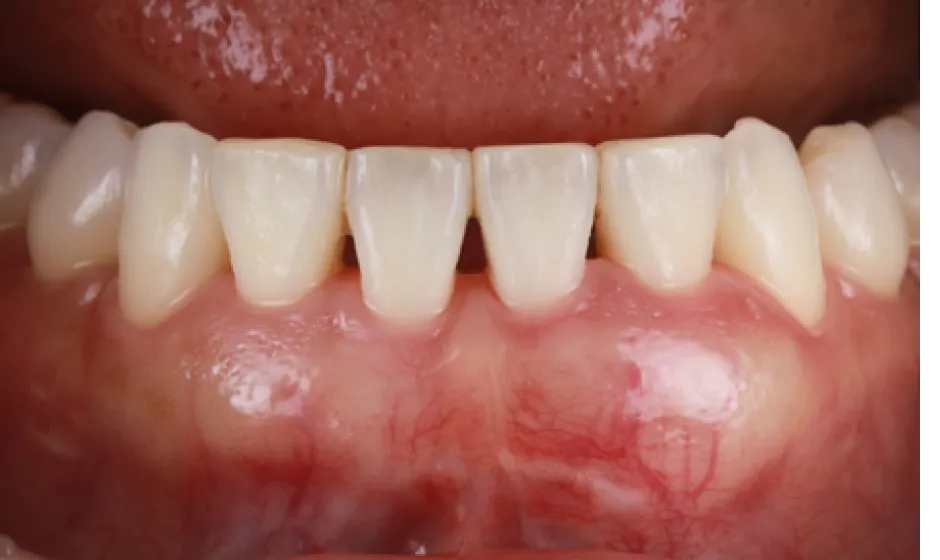

症例2

- 治療名

- 【高度審美形成】歯間乳頭再建術

- 患者様

- 40代女性

- 執刀医

- Dr. 大杉

- 治療期間

- 約1年

- 治療費

- 300,000円(税込)

- リスク

- 移植組織の定着後も、メンテナンスが予後を大きく左右します。

特に歯間ブラシの不適切な使用や過度なブラッシング圧は組織の退縮を招くため、術後は当院の指導に基づいた厳密なプラークコントロールが必要です。